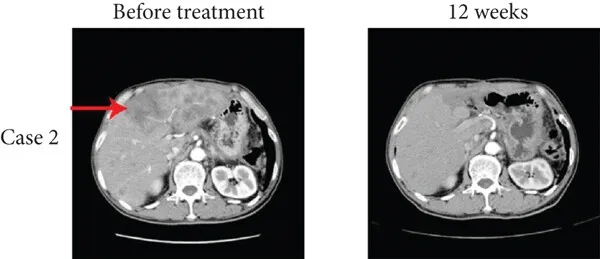

其中1例为一位15岁男性肺转移患者,在接受TIL疗法联合抗PD-1疗法12周后,达到完全缓解(CR),多发性肺转移灶消失(详见下图a),中位无进展生存期(PFS)为15个月。

▲图源“J Immunol Res”,版权归原作者所有,如无意中侵犯了知识产权,请联系我们删除

另一例为20岁男性肝转移患者,经12周TIL联合纳武利尤单抗治疗后,达到完全缓解(CR),肝转移灶消失(详见下图b),中位无进展生存期(PFS)为12.1个月。